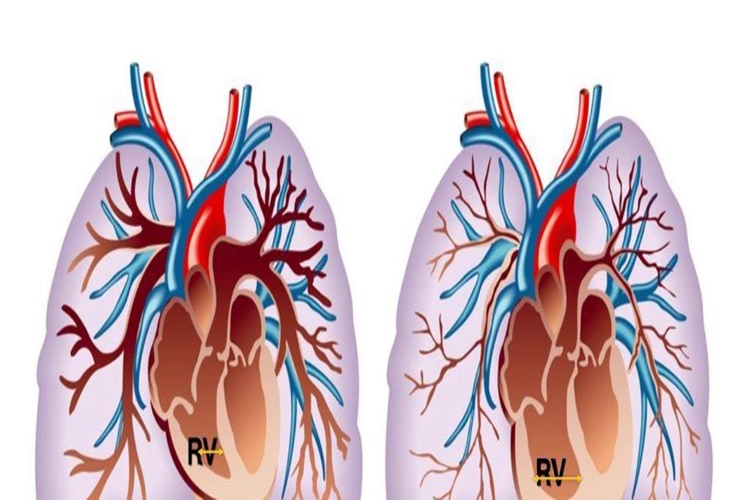

Omurilik tümörü ameliyatının düzensiz kalp ritmi gibi

kardiyak komplikasyonlara yol açma gibi düşük bir riski bulunmaktadır. Omurilik

tümörü beyne, solunum merkezine ya da kalbe yakın olan bir bölgeye yerleşmişse

hasta için ameliyat esnasında ölüm riski bulunabilmektedir.